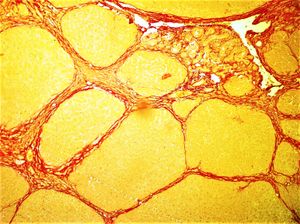

교량 섬유화는 만성 간 질환의 진행 형태에서 나타나는 간 섬유화의 진행된 단계이다. "교량(bridging)"이라는 용어는 문맥 영역에서 중심 정맥까지 성숙하고 두꺼운 섬유 조직 띠가 형성되는 것을 의미한다. 이러한 형태의 섬유화는 가성 소엽 형성을 초래한다. 티오아세트아미드, 사염화탄소, 디에틸니트로사민과 같은 간독성 물질에 장기간 노출되면 실험 동물 모델에서 교량 섬유화를 유발하는 것으로 나타났다.[8][26]